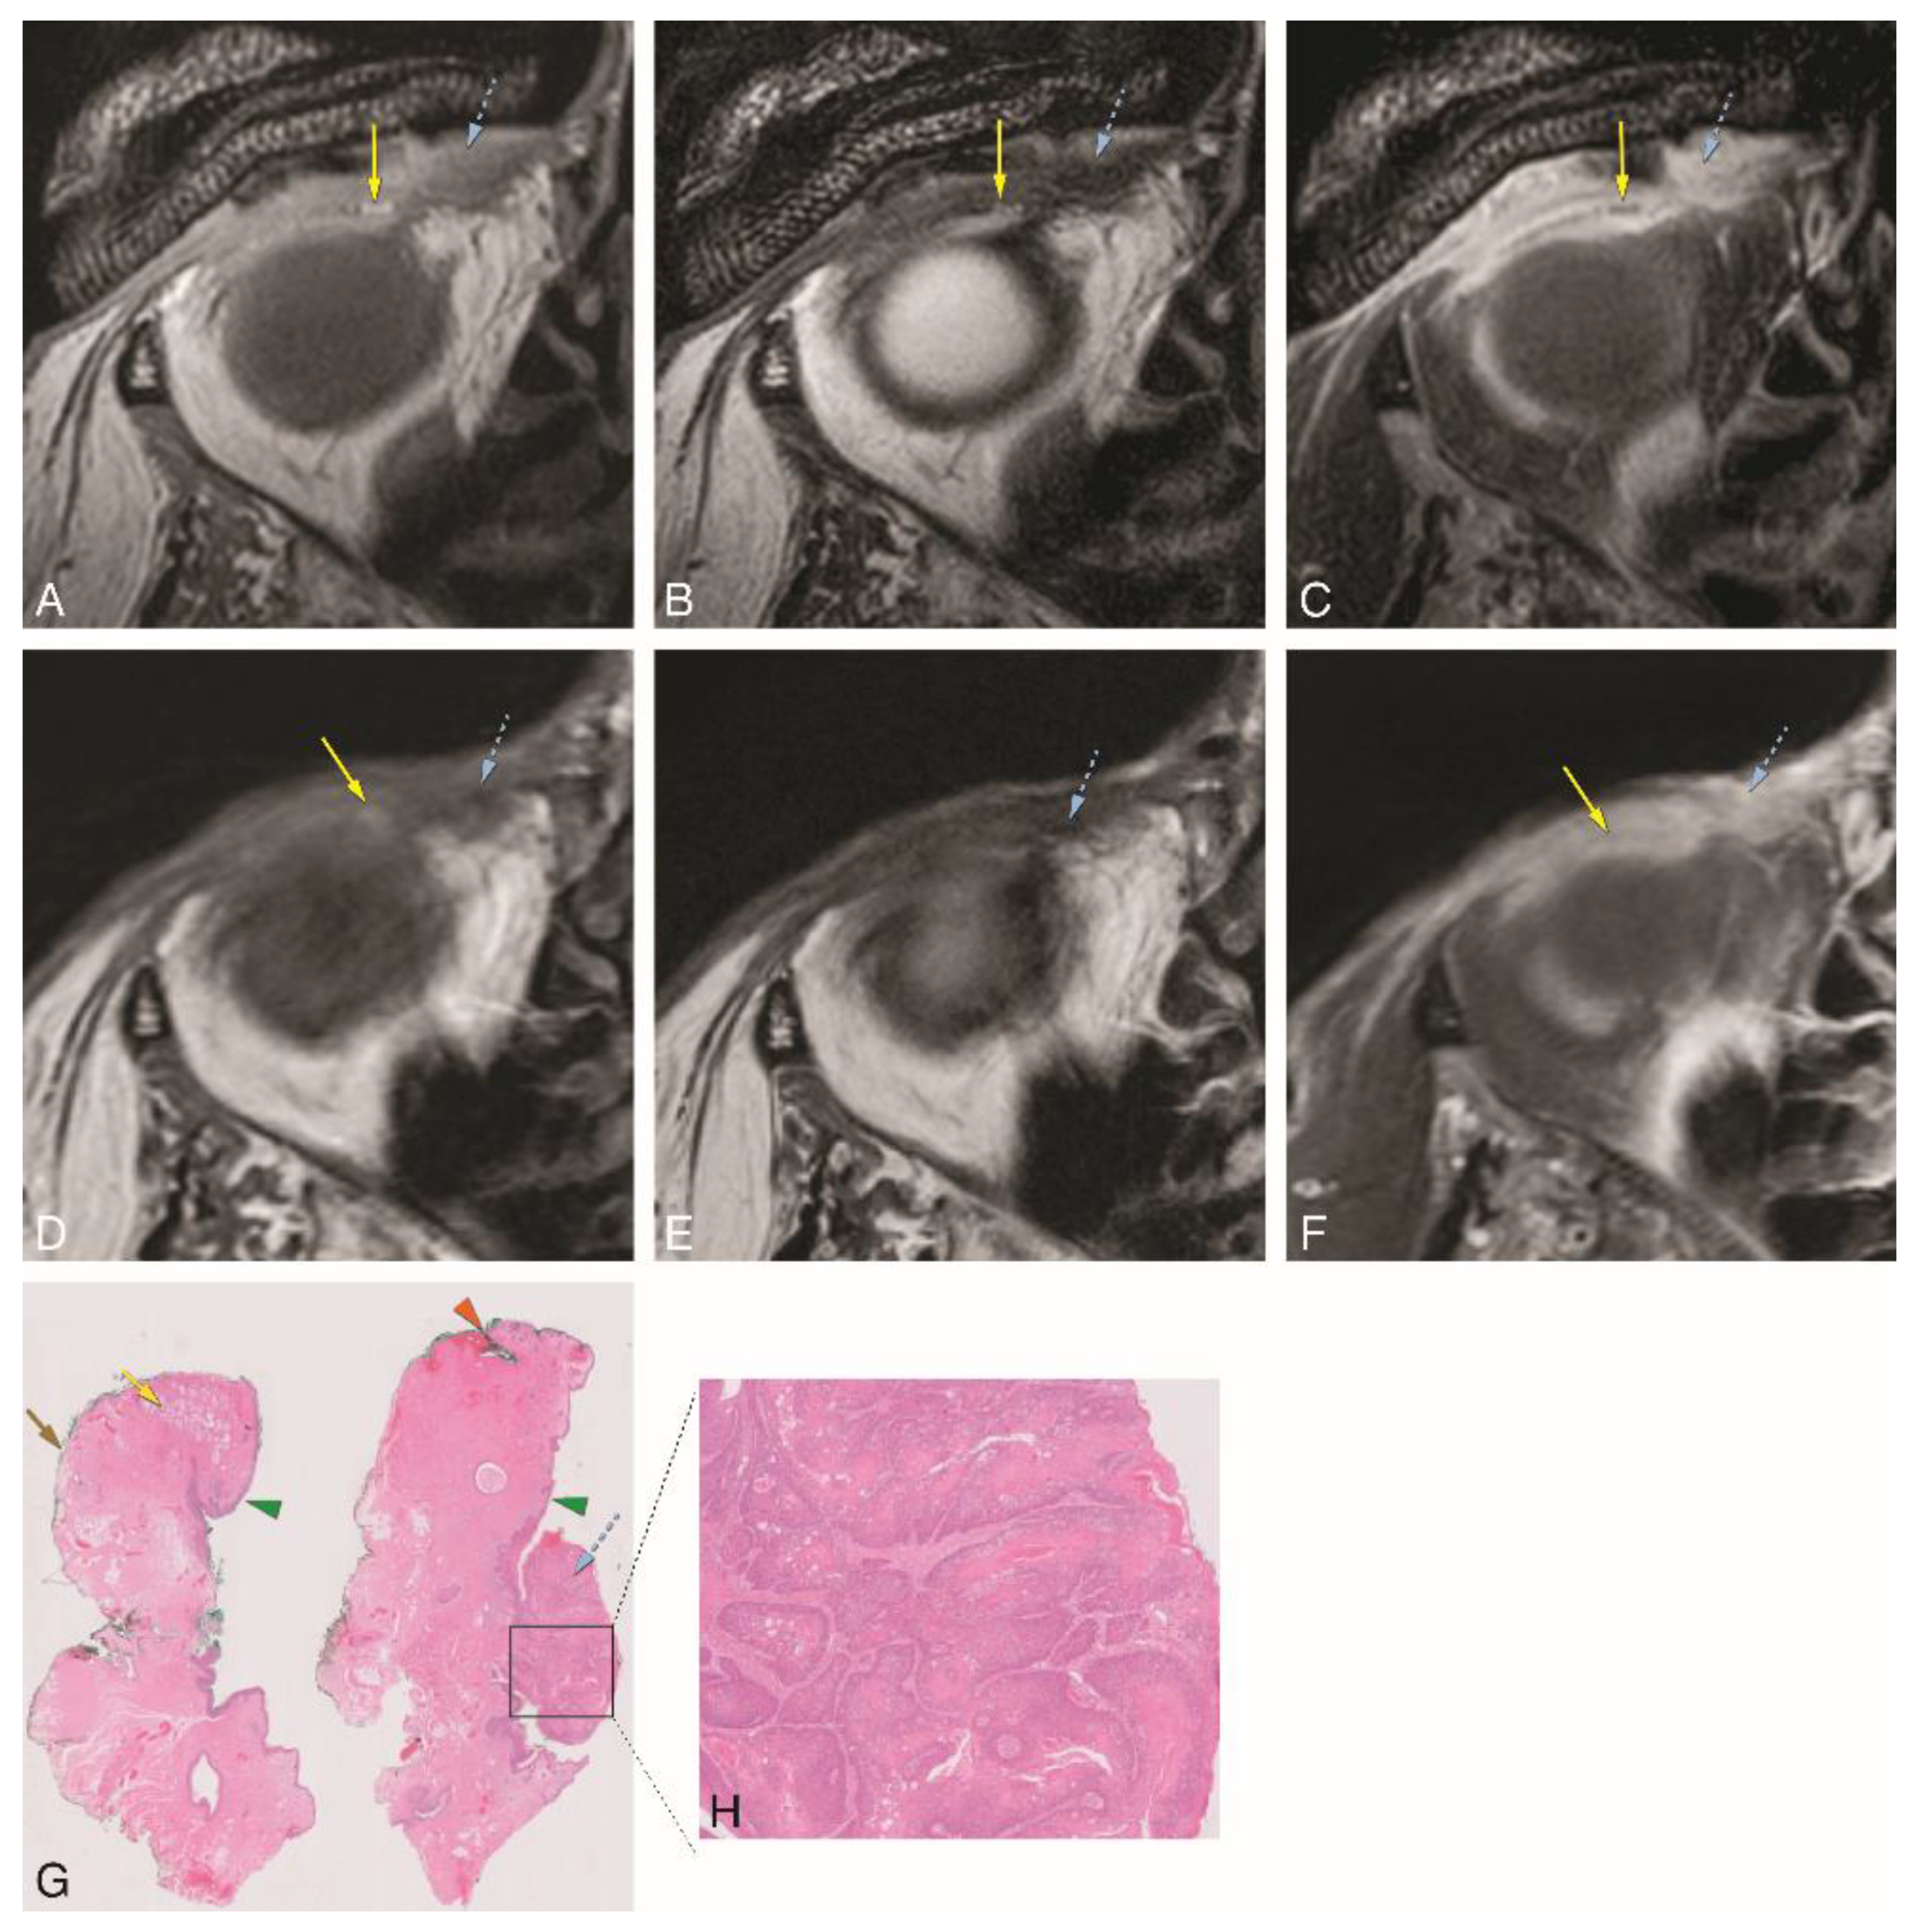

In patient #3, the MRI with a dedicated eyelid protocol (Figure 7) showed post-surgical changes at the medial inferior left eyelid (not shown), due to resection of a melanotic melanoma of the bulbar conjunctiva of the medial inferior eyelid, performed 4 weeks earlier. MRI failed to show the residual/recurrent tumor at the palpebral conjunctiva of the superior left eyelid, depicting intact tarsal plate and orbital septum (Figure 7A–C). The second surgery included removal of the total palpebral conjunctiva, tarsal plate, and margin of the upper eyelid, preserving the upper eyelid skin and part of the orbicularis muscle. Histopathology showed epithelioid cell melanoma confined to the conjunctival epithelium, with free margins (Figure 7D–F). Further surgery was then performed one week later with eyelid reconstruction using a free tarsoconjunctival graft from the contralateral eyelid.

Figure 7. A–F: Patient #3 of Group 3 with a melanotic melanoma of the left superior tarsal conjunctiva (dedicated eyelid protocol). A–C: Sagittals T1-WI (A), T2-WI (B), and contrast-enhanced T1-WI with fat signal suppression (C). It is not possible to visualize the tumor as it is too superficial in the conjunctiva. D-F: Histopathological examination H&E stain (1×) (D), histopathological examination Melan-A stain (1×) (E), and histopathological examination Melan-A stain (40×) (F). Notice the epithelioid cell melanoma (blue dashed arrow) confined to the conjunctiva epithelium. Blue dashed arrow—tumor; purple arrow: palpebral fissure; green arrowhead: skin; orange arrow: orbicularis oculi muscle; yellow arrow: superior and inferior tarsal plates; blue arrow: superior and inferior orbital septa; orange arrowhead: eyelid margin; red arrow: levator palpebrae muscle; grey arrow: superior rectus muscle; white asterisk: inferior oblique muscle; yellow asterisk: inferior eyelid fat protrusion.